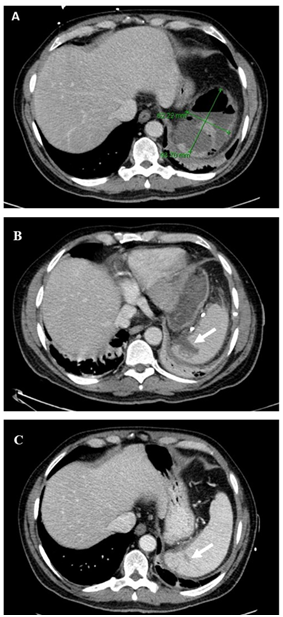

52-year-old Caucasian male with a past medical history of uncontrolled diabetes mellitus type 2 due to medication noncompliance, hypertension, and hypercholesterolemia, presented with two weeks of flu-like symptoms including fevers, night sweats, myalgias, and left lower back discomfort. He denied any symptoms of nausea, diarrhea or vomiting, as well as any history of travel outside the country. On physical exam, patient was febrile with a temperature of 38. 6degree C, tachycardic with a heart rate of 122beats per minute, blood pressure of 122/80mmHg, respiratory rate of 18 breaths per minute and oxygen saturation of 96 % on room air. There was no tenderness to palpation on abdominal examination. Labs were significant for a white blood cell (WBC) count of 16.4K/µL, hemoglobin A 1c of 12.2 %, alkaline phosphatase of 464U/L, alanine transaminase of 232U/L, aspartate amino transferase of 478U/L. CRP was elevated at 178.9mg/L. He tested negative for HIV and hepatitis A, B and C. Blood cultures were collected. Abdominal computerized tomography (CT) scan showed an enlarged spleen measuring 14cm with a gas and fluid containing collection measuring approximately 6.2x9.4x5.6cm suggestive of splenic abscess with adjacent free fluid and fat stranding abutting the diaphragm (Figure 1A). Patient was started on 2g intravenous (IV) ceftriaxone daily. Blood cultures obtained on the day of admission subsequently grew Salmonella typhimurium. Transesophageal echocardiography was negative for vegetations. A percutaneous drain was placed the following day and the patient’s symptoms significantly improved. CT scan on day six of IV antibiotics showed a decrease in size of the original splenic abscess, with identification of an additional smaller splenic abscess (Figure 1B). Patient was discharged on outpatient IV ceftriaxone for a total of six weeks, along with optimal glycemic control of his diabetes. A follow up CT scan after five weeks of treatment showed near resolution of the splenic abscesses (Figure 1C). The percutaneous drain was removed. Follow-up blood cultures at two and four weeks after completion of antibiotic treatment were negative.

Figure 1 Figure 1 (A)Abdominal CT scans from day 1showing splenomegaly measuring 14 cm with a gas and fluid containing collection measuring approximately 6.2 x 9.4 x 5.6 cm and adjacent free fluid and fat stranding abutting the diaphragm (marked with green arrows). (B) Day 6 of antibiotic therapy and drainage where the initial abscess has decreased in size to 3.0 cm x 2.9 cm. An additional 1.4 x 2.9 cm perisplenic abscess was noted in the sub diaphragmatic space. (C) Follow up scan on day 24 of antibiotics showed thin crescent of fluid or granulation tissue deep to the splenic parenchyma and measuring up to 0.5 cm in thickness.